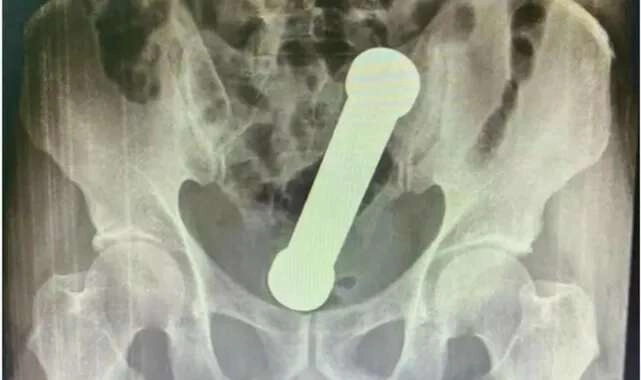

Brezilya’da yaşanan inanılması zor olayda; doktorlar, kramp ve şiddetli kabızlık şikâyeti ile acile giden 54 yaşındaki adamın röntgen filmi çıktığında gözlerine inanamadı. Röntgen filminin sonucuna göre 54 yaşındaki adamın rektumunda iki kiloluk bir dambıl vardı.

Brezilya’da yaşanan ilginç olayda, doktorlar, kramp ve şiddetli kabızlık şikâyeti ile acile gelen bir erkek hastanın rektumunda iki kiloluk dambıl bulunca şok oldular. Muayene esnasında belli olmayan durum, hastanın röntgen filmi çekilince ortaya çıktı. Brezilya’nın Manaus kentinde yaşanan olayda sağlık görevlileri, cımbız kullanarak nesneyi dışarı çıkarmaya çalıştılar ancak başarısız oldular. Sonrasında daha acımasız bir yönteme başvurdular ve elle çıkarmayı denediler.